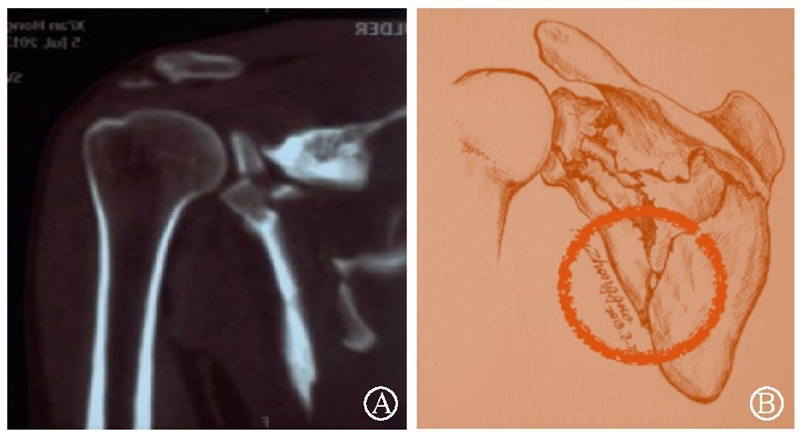

病例2为1例累及肩胛盂、肩胛颈和肩胛骨体部的复杂肩胛骨骨折(图11-12)。

术前设计采用跨骨折区域钢板螺钉固定(图13)。术中可见纵向骨折区域骨质薄弱,骨折粉碎严重,钢板放置位置有限,操作极其困难(图14)。术中采用多块接骨板跨骨折区域固定,术后X线片及三维CT重建显示复位满意(图15)。针对此病例,如果采用缝线辅助固定技术,可使手术操作过程简化,达到同样的固定效果(图16)。

图11 CT三维重建及轴位重建示肩胛骨骨折累及肩胛盂、肩胛颈和肩胛骨体部 图A:CT三维重建;图B:CT轴位重建

图12 CT冠状位重建及手绘示意图重现骨折累及肩胛盂、肩胛颈及肩胛骨体部 图A:CT冠状位重建;图B:手绘示意图